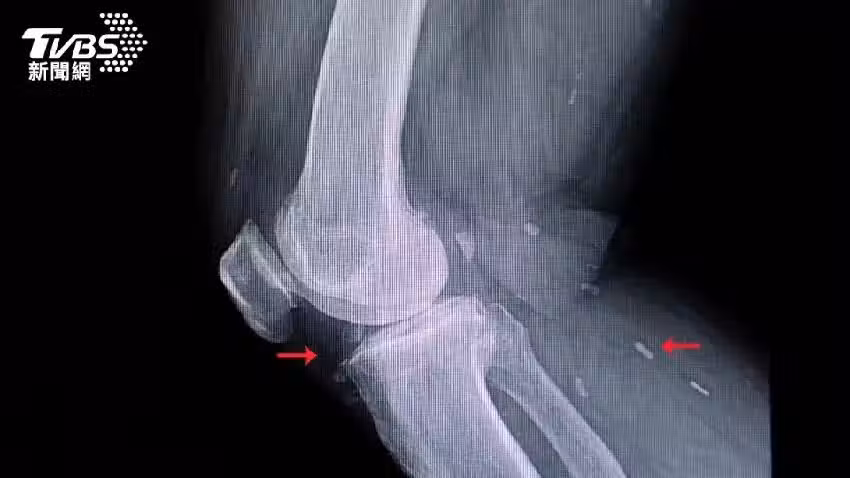

根據《每日郵報》報導,絛蟲的幼蟲可能進入肌肉甚至大腦等組織,它們被身體的免疫系統殺死後,會形成硬化的囊腫,在皮膚下可以摸到像腫塊一樣,在醫學掃描中會呈現出如白色橢圓形的「米粒」。